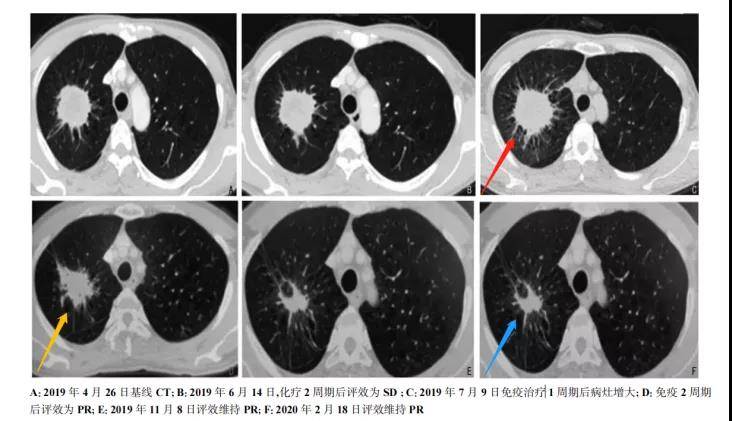

《中国肿瘤临床期刊》记录了一例患有肺腺癌的55岁男性,于2019 年 4 月 26 日采用化疗方案,化疗2周期后疾病稳定(备注:1周期一般为21天),于第3周期开始加用免疫治疗(此处特指免疫检查点抑制剂),免疫治疗1周期后患者出现咳嗽加重、咯血、右侧胸痛、四肢关节肿胀、疼痛明显等症状,后行CT检查(图1),右肺内病灶增大。

图片 图1 患者治疗期间CT检查

于是,该案例经多学科会诊后,专家们考虑不排除“假性进展”,故行肺部病灶穿刺活检,看到肺腺癌伴大量坏死及淋巴细胞浸润(图2),证实为假性进展,遂继续当前治疗方案,免疫治疗2周期后病灶缩小,达到部分缓解(PR)。患者于2020 年 2 月 18 日复查维持 PR 状态,并继续使用免疫治疗药物维持。在后续治疗过程中,患者未再出现关节肿痛,也无其他不良反应发生。随访至2020 年 5 月 18 日,未见肿瘤复发转移。